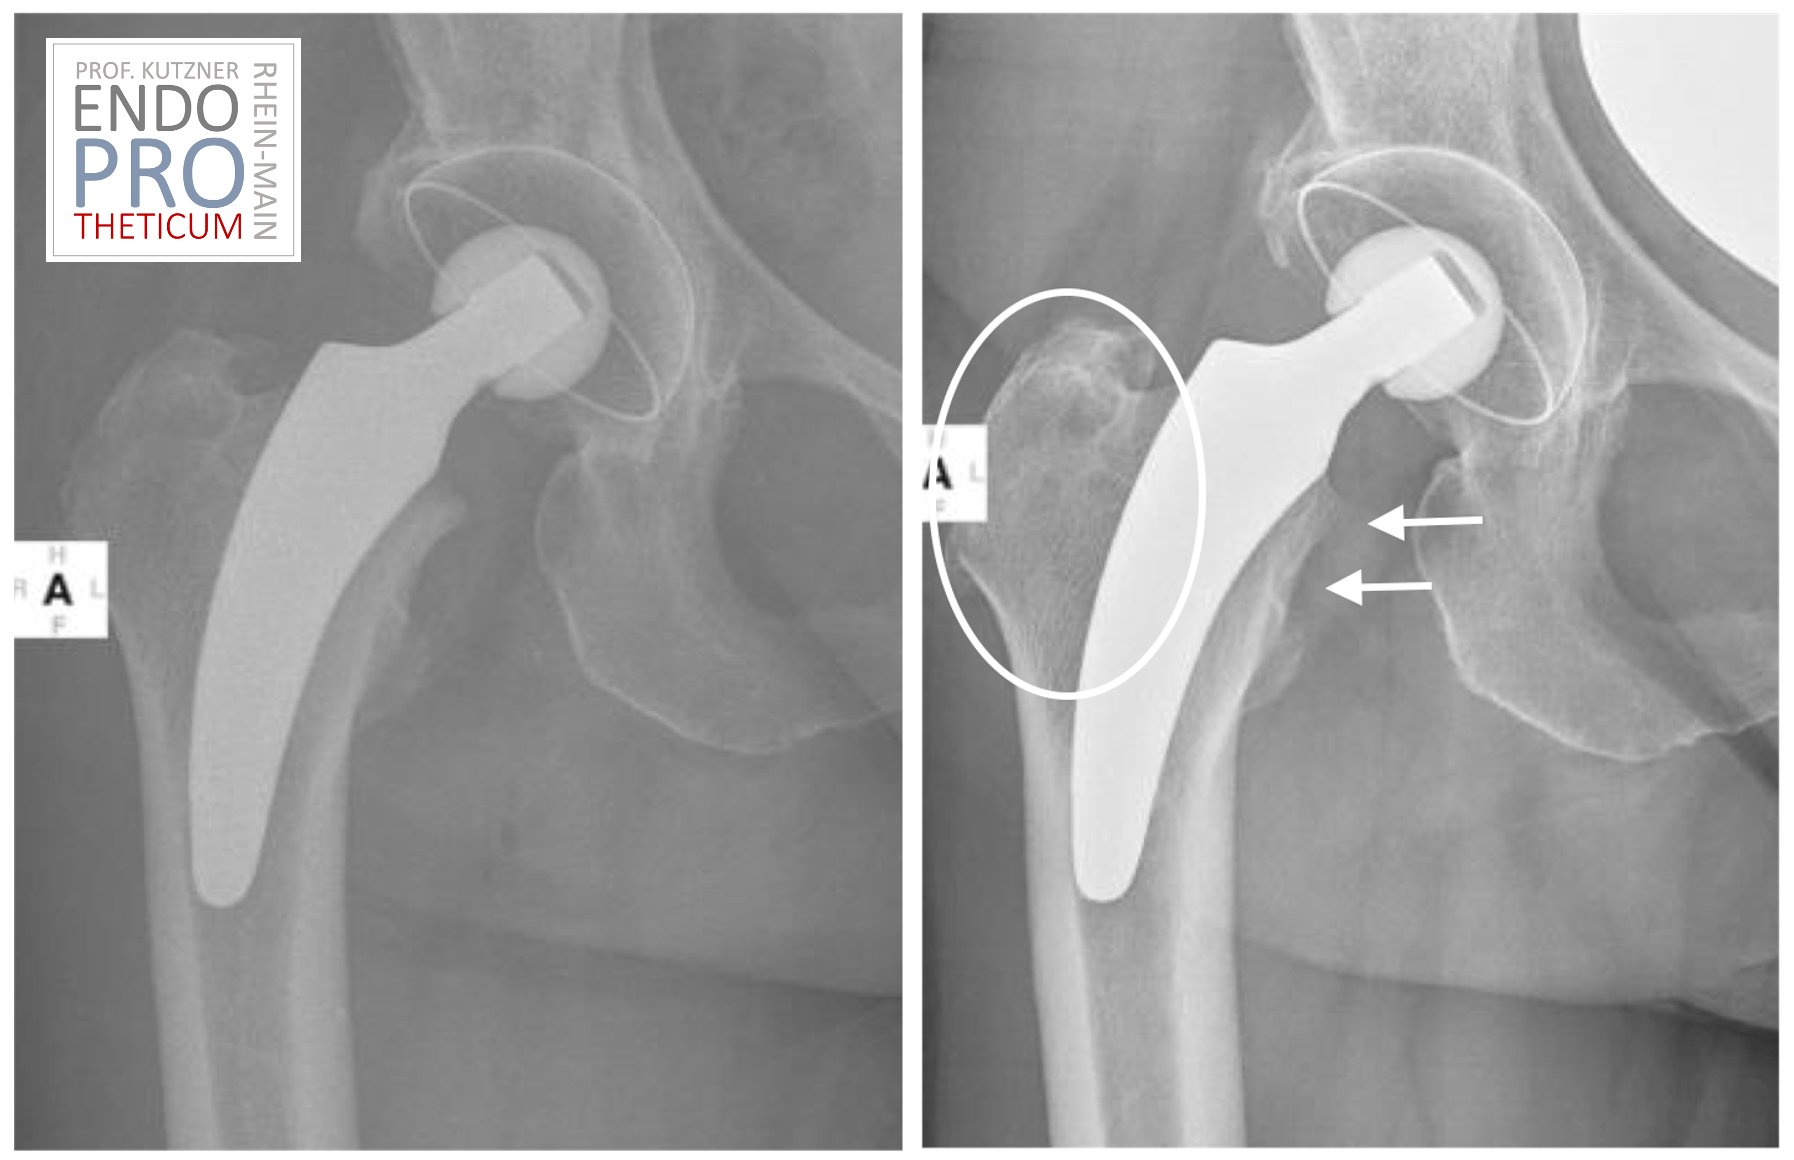

कृत्रिम शॉर्ट-स्टेम प्रोथेसिस विशेष रूप से हिप रिप्लेसमेंट सर्जरी के लिए डिज़ाइन किए गए हैं और पारंपरिक इम्प्लांट की तुलना में एक छोटी स्टेम लंबाई होती है। इन्हें ऊपरी जांघ की हड्डी में डाला जाता है ताकि क्षतिग्रस्त या रोगग्रस्त ऊतकों को बदल दिया जा सके और कूल्हे के जोड़ के कार्य को बहाल किया जा सके। कृत्रिम शॉर्ट-स्टेम प्रोथेसिस कूल्हे के जोड़ की स्थिरता और गतिशीलता में सुधार करते हैं, जिससे तेजी से रिकवरी और कम पोस्टऑपरेटिव जटिलताएं हो सकती हैं।.

कुछ रोगियों के लिए शॉर्ट-स्टेम प्रोथेसिस कई संभावित लाभ प्रदान करते हैं। इनमें न्यूनतम इनवेसिव सर्जिकल तकनीक के कारण तेजी से रिकवरी, कूल्हे के जोड़ की बेहतर स्थिरता और सर्जरी के बाद डिस्लोकेशन या लक्सेशन की कम संभावना शामिल है। इसके अलावा, उन्हें अक्सर सर्जरी के दौरान कम हड्डी हटाने की आवश्यकता होती है, जो फीमर की अखंडता को बनाए रख सकती है।.

यद्यपि शॉर्ट-स्टेम प्रोस्थेसिस कई संभावित लाभ प्रदान करते हैं, वे हर रोगी के लिए उपयुक्त नहीं हैं। सभी चिकित्सा प्रक्रियाओं की तरह, शॉर्ट-स्टेम प्रोस्थेसिस के उपयोग में भी जोखिम और जटिलताएं होती हैं, जिनमें संक्रमण, रक्त के थक्के और इम्प्लांट की ढीलापन शामिल हैं। इन जोखिमों पर अपने डॉक्टर से चर्चा करना और यह निर्धारित करने के लिए एक गहन जोखिम-लाभ विश्लेषण करना महत्वपूर्ण है कि क्या शॉर्ट-स्टेम प्रोस्थेसिस आपके लिए सही विकल्प है।.